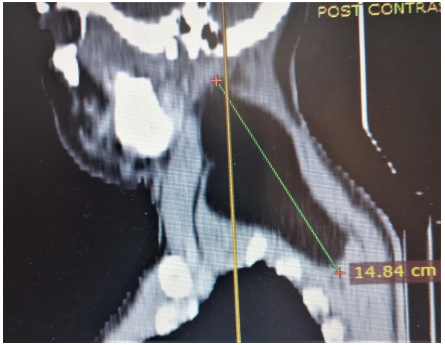

The computed tomogram of the neck showed a hypodense (HU = -109) mass demonstrated in the left paraspinal space of the neck extending from the level of C2 to T1 vertebrae and from posterior to anterior aspect of the neck. It measures about 148 x 97 x 59 mm in its widest craniocaudal, antero-posterior and transverse dimensions respectively (figure, 1 and 2). It shows well outline margin and thin internal septae. There is some enhancement of the septae and the margin of the mass in the post contrast series. No calcification was demonstrated within the mass. There is displacing the adjacent muscles. Anterior displacement of the internal jugular vein and common carotid artery was noted. No intrathoracic extension is demonstrated. No lymphadenopathy is demonstrated. A diagnosis of giant left side neck (paraspinal space) lipoma was made.

Figure 1: Computed tomogram of the neck sagital plane showing a giant fat density mass (lipoma) deep in the posterior aspect of the neck (arrow)

The benign lipomas are the most common of all mesenchymal tumours [2]. They may be located in all parts of the body and may be classified anatomically as superficial or deep [2]. Most of the head and neck lipomas are superficial and are found in the posterior region of the neck. Deep neck lipomas are rare [2]. The index case is a deep lipoma located predominantly in the posterior aspect of the neck and extends to the anterior region (figure. 2). A Giant lipoma is when a lipoma grows to a size of atleast 10 cm in one dimension or weighs a minimum of about 1000 g as demonstrated in this case (figure 1). Lipomas may occur sporadically or as part of an inherited disease such as familial multiple lipomatosis [5]. They may also occur secondary to trauma with rupture of the fibrous septae inducing adipose tissue migration and proliferation [5].

Imaging plays vital role in evaluation of lipoma. Diagnostic imaging employed, include ultrasonography, plain radiography, computed tomography (CT) scan or magnetic resonance imaging (MRI). The cross sectional imaging (CT and MRI) though not readily available has the advantage of assessing the exact location, size and relationship with surrounding structure. [1,2]. They can also help in differentiating benign lipomas from malignant lipomas. On imaging lipomas are well-defined mass of mature fat (adipocytes) and appears as radiolucent on radiographs, low attenuation on CT with Hounsfield Unit (HU) of -65 to -120 (fig, 1 and 2) and hyperintense on T1-weighted MRI. Fine septations can be seen on both CT and MRI. Features that suggest malignancy include thick capsule, ill-defined border, thick or nodular septations, prominent areas of high T2 signal on MRI and prominent areas of enhancement in the post contrast phase [1,2].